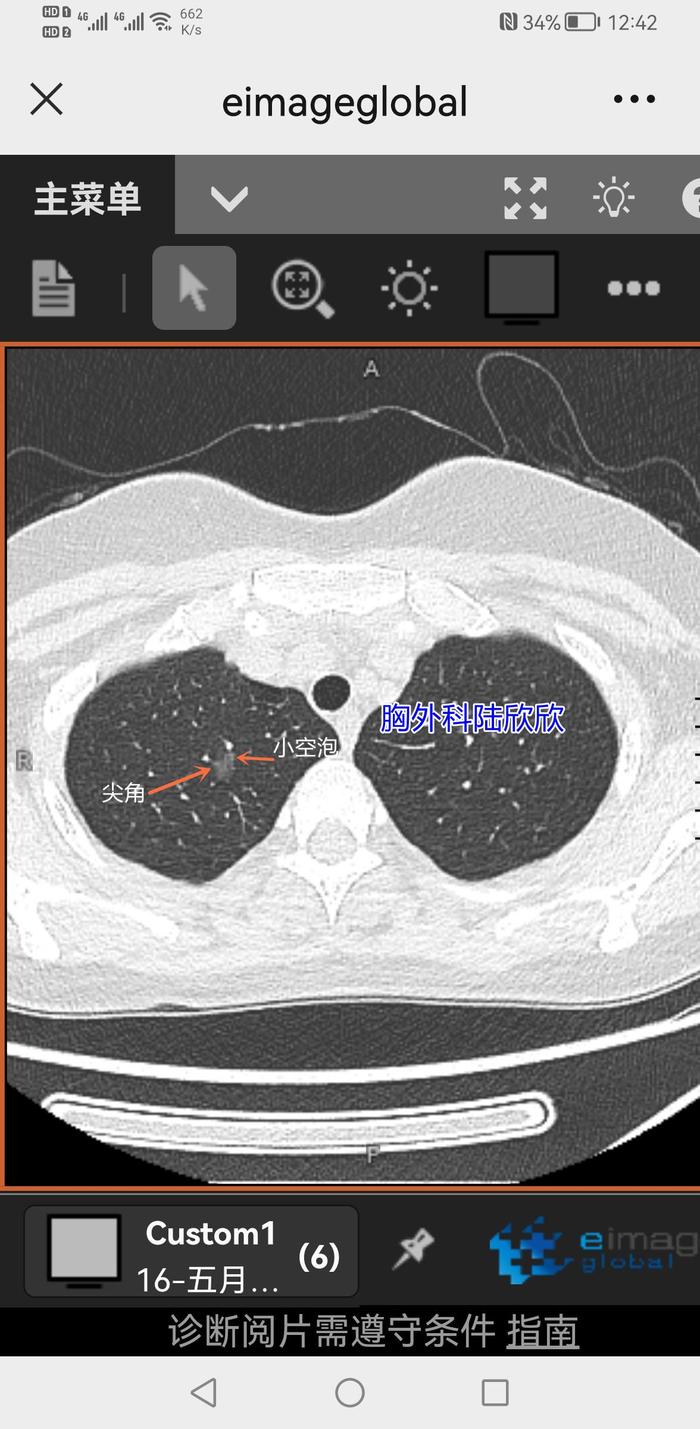

我对病人说:“你的右上肺有一个磨玻璃结节。最大径大约是10毫米。形状不是规则的球形,不是椭圆形。边界有点不规则。局部突起像是一个尖角。”我把手机上磨玻璃结节的尖角指给病人看。

我接着对病人说:“你的右上肺的磨玻璃结节,里面有两个发暗的地方,是两个小空泡,一个空泡明显一些,另外一个不明显。”我把手机上磨玻璃结节的小空泡指给病人看。

下面是我那天门诊手机上的截图:

上图可能保存放大后看更清晰。